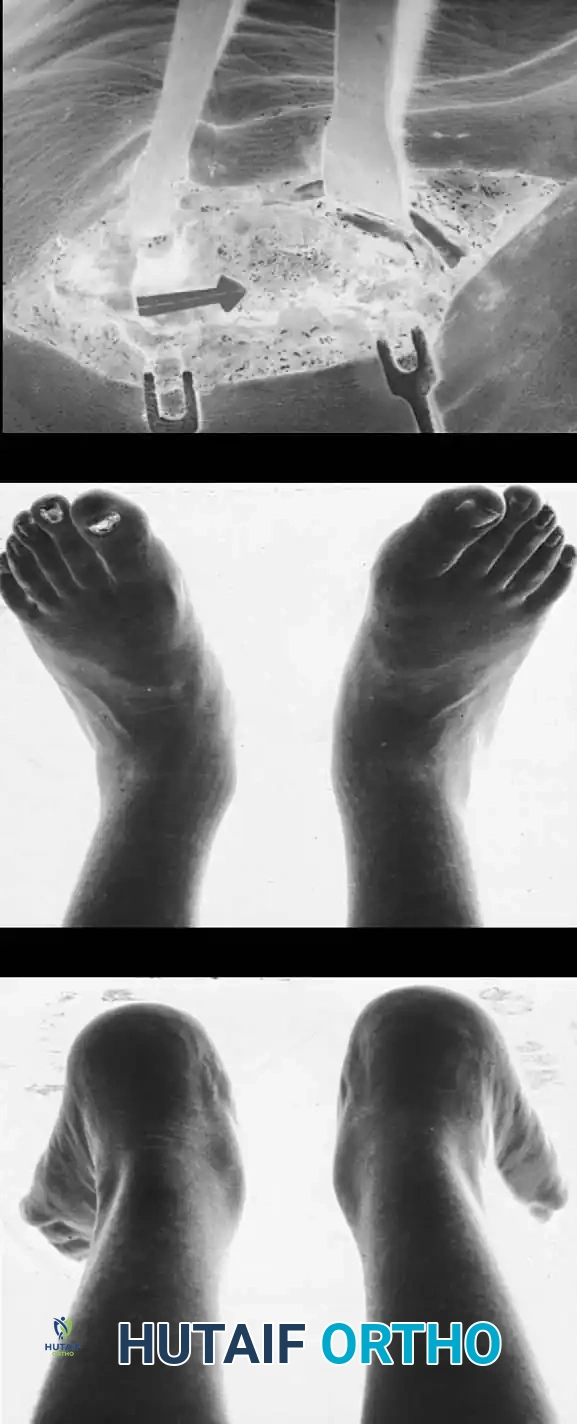

جراحة إزالة التحام العقب والزورقي

في حالة التحام العقب والزورقي، يعتبر الاستئصال الجراحي للجسر العظمي هو الخيار المفضل، خاصة لدى الأطفال والمراهقين الذين لا يعانون من خشونة في المفاصل.

يقوم الجراح بإزالة الجسر العظمي بالكامل لضمان عدم عودته. ولمنع تكوّن العظم مرة أخرى في نفس المكان، يتم وضع نسيج عازل في الفراغ الناتج، مثل جزء من عضلة مجاورة (Extensor digitorum brevis) أو نسيج دهني، أو استخدام الشمع الطبي. أثبتت الدراسات أن هذه الجراحة تنجح بنسبة عالية في تخفيف الألم واستعادة جزء كبير من حركة المفصل.

جراحة إزالة التحام الكاحل والعقب

تُجرى هذه العملية عادة للمرضى الأصغر سناً (10 إلى 15 عاماً) عندما يكون الالتحام في المفصل الأوسط (Middle Facet) صغيراً (أقل من 50% من مساحة المفصل) ولا توجد علامات على خشونة المفاصل.

يتم الدخول جراحياً من الجهة الداخلية للقدم، ويتم استئصال الجسر العظمي بدقة باستخدام أدوات دقيقة حتى يظهر الغضروف السليم للمفصل. كما هو الحال في الالتحام السابق، يتم وضع نسيج دهني أو شمع عظمي لمنع الالتصاق مجدداً.